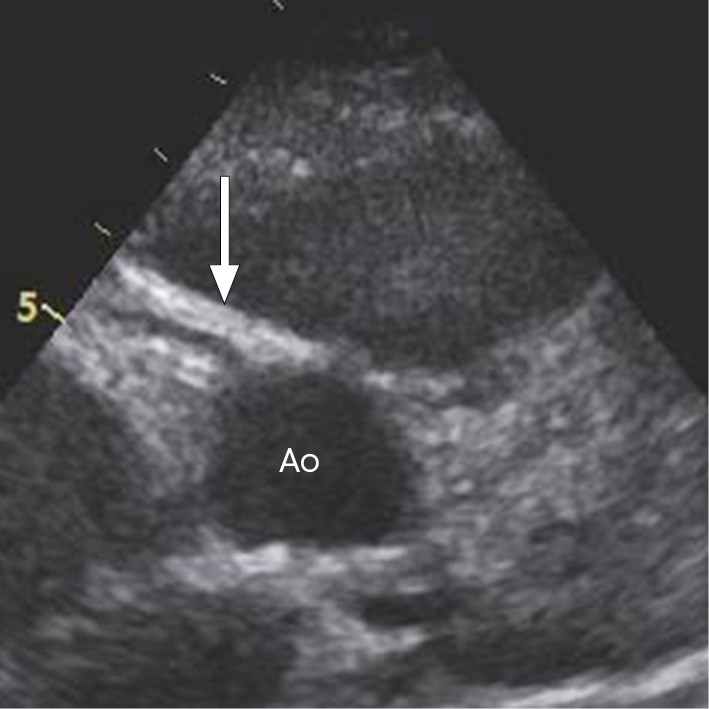

Ekkokardiografi viste initialt redusert systolisk funksjon av venstre ventrikkel, med forkortningsfraksjon (FF) på 20 % (M-modus fra parasternal posisjon) og global longitudinell strekkbarhet (global longitudinal strain, GLS) på −12 % (fra apikal firekammerposisjon). Det var ikke tegn til dilatasjon av venstre ventrikkel og heller ikke tegn til pulmonal hypertensjon. Forkortningsfraksjon mindre enn 25 % og GLS mer enn −16 % indikerer signifikant myokardial dysfunksjon.

Dag 4 viste ekkokardiografi økt ekko i koronarveggen, som kan være et tidlig tegn på koronaraffeksjon (figur 1). Inflammasjonsmarkørene hadde falt fint etter første dose immunglobuliner, men feberen vedvarte. Man startet derfor med acetylsalisylsyre 500 mg × 4 per døgn peroralt. Dag 5 ble det gitt en ny ekvivalent dose immunglobuliner, hvorpå pasienten ble afebril.